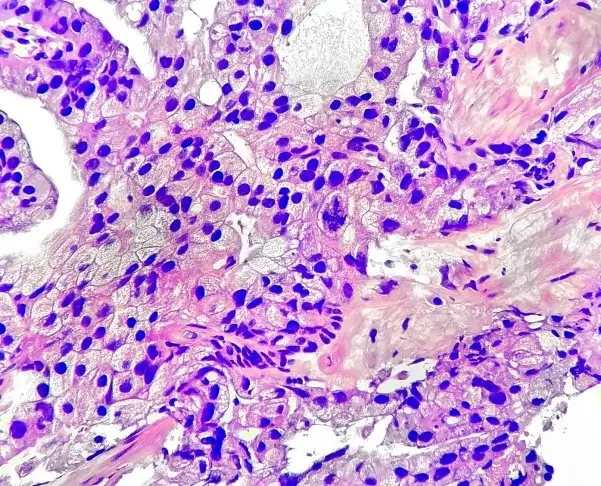

- Multimodal AI (MMAI) Models: Deep learning models trained on diverse, large-scale clinical trial data (NRG Oncology phase III trials) to provide prognostic and predictive insights from digitized histopathology slides.

Artera uses multimodal artificial intelligence (MMAI) — deep learning models trained on digitized histopathology images and clinical data from large-scale phase III oncology trials — to generate prognostic and predictive scores for individual patients.